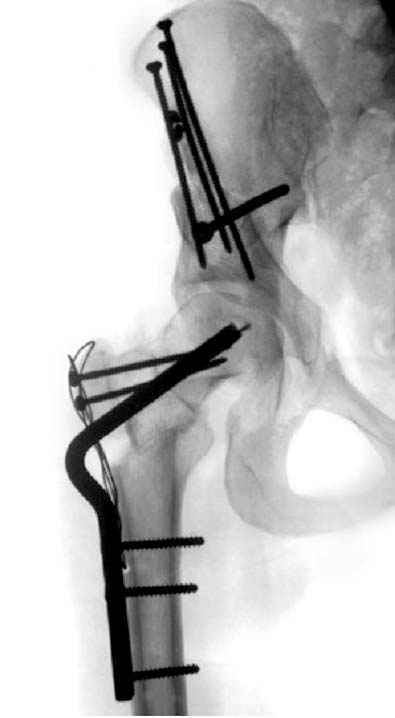

после операции при дисплазии тазобедренного

сустава #4

сустава #5

№ 4-6 после операции при дисплазии тазобедренного

сустава